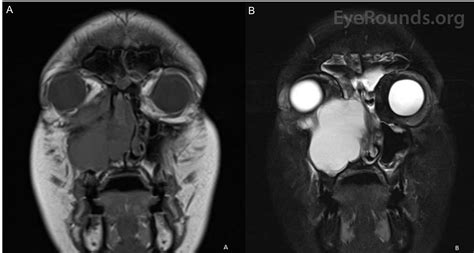

MRI Used in complex cases to determine the nature of the fluid content within the cyst.

Since these cysts rarely present with overt symptoms, diagnosis is almost always achieved through imaging. When your dentist or ENT specialist identifies a potential Cyst Sinus Maxillaris, they will use advanced imaging technology to differentiate it from other, more serious pathologies.